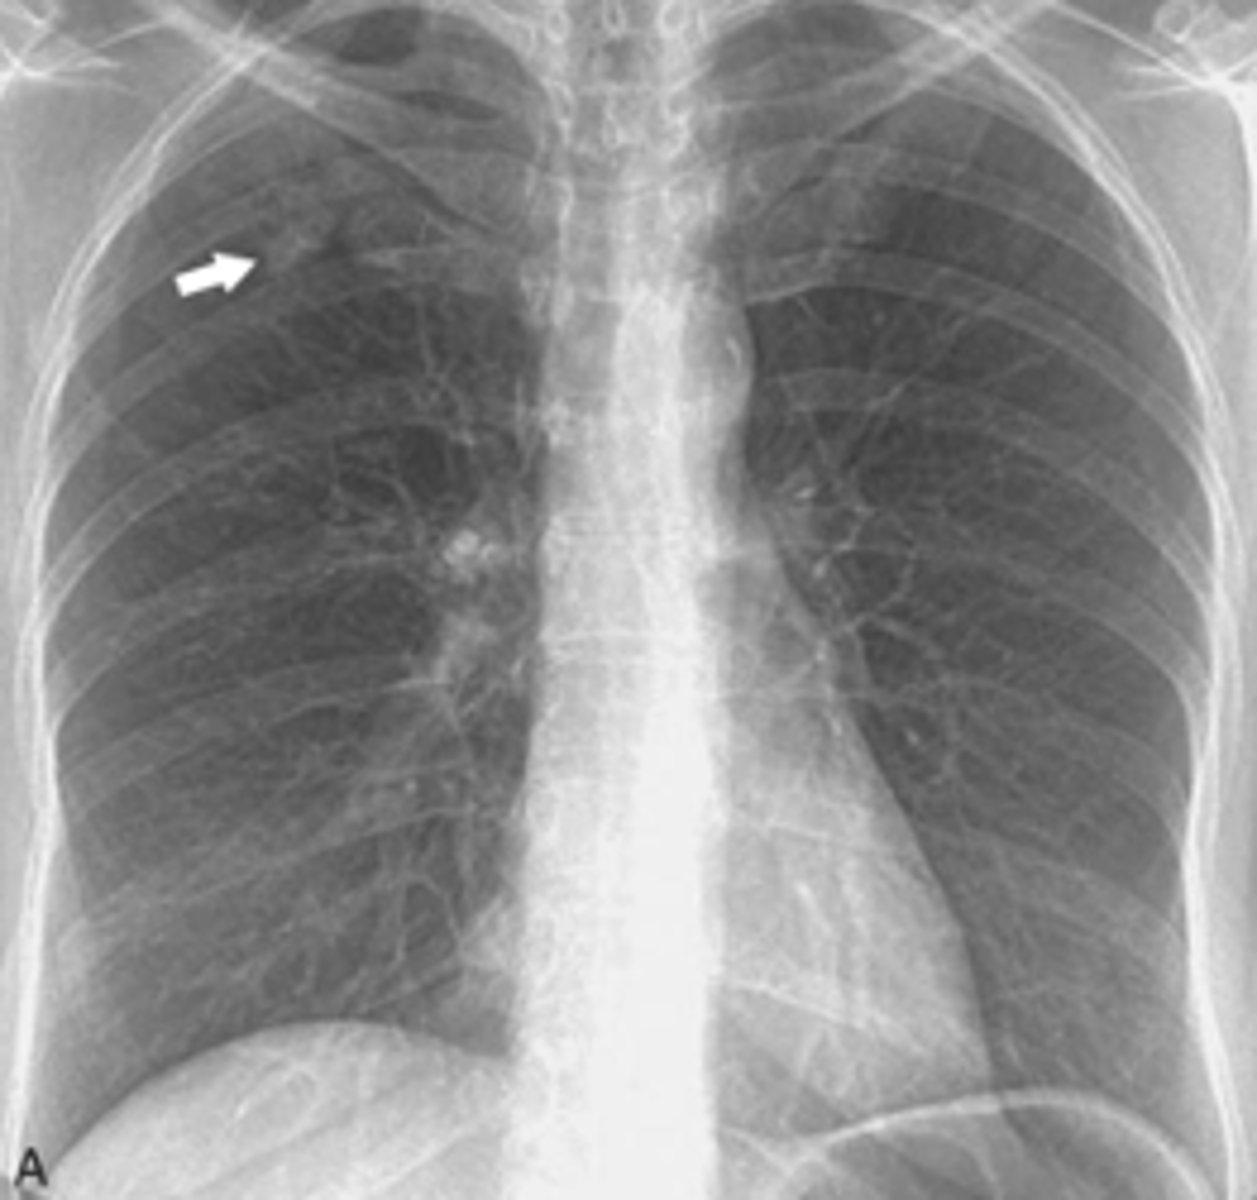

ID Ghon and Ranke complexes on xray

There is a combination of a calcified peripheral granuloma (black arrow) and a calcified hilar lymph node (white arrow) on the same side. Several other, small calcified granulomas are seen in the right mid-lung field - ranke complex

ranke typically more dense

<p>There is a combination of a calcified peripheral granuloma (black arrow) and a calcified hilar lymph node (white arrow) on the same side. Several other, small calcified granulomas are seen in the right mid-lung field - ranke complex</p><p>ranke typically more dense</p>